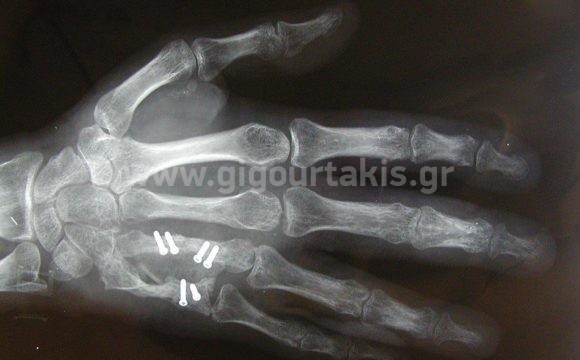

ΒΑΡΥ ΤΡΑΥΜΑ ΠΕΡΙΣΤΑΤΙΚΟ 1 01. 02. 03. 04. ΑΡΧΙΚΗ ΚΑΜΨΗ ΔΑΚΤΥΛΩΝ 05. ΑΡΧΙΚΗ ΕΚΤΑΣΗ ΔΑΚΤΥΛΩΝ ΠΕΡΙΣΤΑΤΙΚΟ 2 01. 02. 03. 04. 05. ΕΚΤΑΣΗ ΔΑΚΤΥΛΩΝ 06. ΚΑΜΨΗ ΔΑΚΤΥΛΩΝ 07. ΠΕΡΙΣΤΑΤΙΚΟ 3 01. 02. 03.ΤΕΛΙΚΗ ΚΑΜΨΗ ΔΑΚΤΥΛΩΝ 04.ΤΕΛΙΚΗ ΕΚΤΑΣΗ ΔΑΚΤΥΛΩΝ 05. ΠΕΡΙΣΤΑΤΙΚΟ 4 01. 02. 03. 04. 05.ΚΑΜΨΗ ΔΑΚΤΥΛΩΝ 06.ΠΑΛΑΜΙΑΙΑ ΚΑΜΨΗ ΠΗΧΕΟΚΑΡΠΙΚΗΣ ΔΑΚΤΥΛΩΝ 07. ΕΚΤΑΣΗ ΔΑΚΤΥΛΩΝ 08.ΡΑΧΙΑΙΑ ΚΑΜΨΗ ΠΗΧΕΟΚΑΡΠΙΚΗΣ 09 .ΑΠΑΓΩΓΗ ΔΑΚΤΥΛΩΝ ΠΕΡΙΣΤΑΣΤΙΚΟ 5 01.ΚΑΜΨΗ ΔΑΚΤΥΛΩΝ 02.ΕΚΤΑΣΗ ΔΑΚΤΥΛΩΝ 03.ΕΚΤΑΣΗ ΔΑΚΤΥΛΩΝ 04 ΠΕΡΙΣΤΑΤΙΚΟ 6 01. 02. 03. ΚΑΜΨΗ ΔΑΚΤΥΛΩΝ 04. ΕΚΤΑΣΗ ΔΑΚΤΥΛΩΝ ΠΕΡΙΣΤΑΤΙΚΟ 7 01. 02. ΑΚΤΙΝΟΓΡΑΦΙΑ 03. 04.ΚΑΜΨΗ ΔΑΚΤΥΛΩΝ ΠΕΡΙΣΤΑΤΙΚΟ 8 01. ΑΚΤΙΝΟΓΡΑΦΙΑ 02. ΑΚΤΙΝΟΓΡΑΦΙΑ 03. 04. 05. ΠΕΡΙΣΤΑΤΙΚΟ 9 01. 02.ΑΡΧΙΚΗ ΚΑΜΨΗ ΔΑΚΤΥΛΩΝ 03.ΑΡΧΙΚΗ ΕΚΤΑΣΗ ΔΑΚΤΥΛΩΝ ΠΕΡΙΣΤΑΤΙΚΟ 10 01. ΑΚΤΙΝΟΓΡΑΦΙΑ 02. 03.ΑΡΧΙΚΗ ΚΑΜΨΗ ΔΑΚΤΥΛΟΥ 04. Στις κατηγορίες:ΑΝΩ ΑΚΡΟ, ΑΚΡΑ ΧΕΙΡΑ, ΒΑΡΥ ΤΡΑΥΜΑ